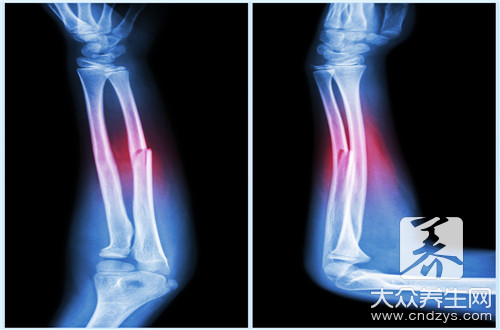

骨折是指骨结构的连续性完全或部分断裂。多见于儿童及老年人,中青年人也时有发生。病人常为—个部位骨折,少数为多发性骨折。经及时恰当处理,多数病人能恢复原来的功能,少数病人可遗留有不同程度的后遗症。

骨折病人的典型表现是伤后出现局部变形、肢体等出现异常运动、移动肢体时可听到骨擦音。此外,伤口剧痛,局部肿胀、淤血,伤后出现运动障碍。

是将骨折后发生移位的骨折断端重新恢复正常或接近原有解剖关系,以重新恢复骨骼的支架作用。复位的方法有闭合复位和手术复位。